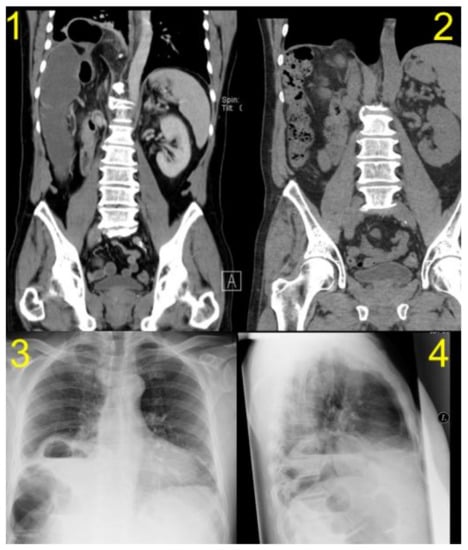

| Diagnostic Study | CT | CT | CT | CT/MRI | CT |

| Herniated organ | right colon flexure, omentum | colon and small bowell | colon and omentum majus | colon | colon |

| Side of hernia | right-sided | right-sided | right-sided | right-sided | right-sided |

| Size of Hernia | 4 cm | <5 cm | 4 cm | 5 cm | 7 cm |